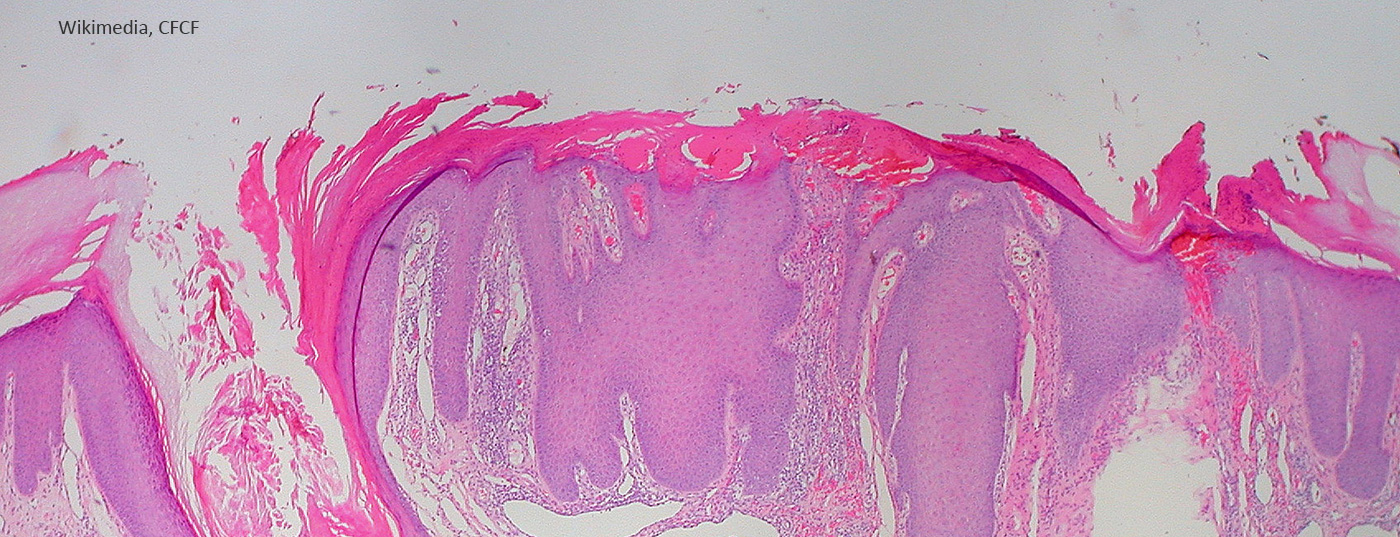

Pruriginöse läsionale Haut weist spezifische DNA-Methylierungssignatur auf

Die Frage, welche Mechanismen bei chronisch nodulärer Prurigo zur Chronifizierung des Juckreizes beitragen, ist Gegenstand aktueller Forschung. Neue Erkenntnisse erhofft man sich aus der Untersuchung molekularer Prozesse. In einem anlässlich der diesjährigen ADF-Tagung vorgestellten Projekt wurden DNA-Methylierungsmuster pruriginös-läsionaler und nicht-läsionaler Haut von Prurigo-Patienten analysiert und mit einer hautgesunden Kontrollgruppe verglichen.